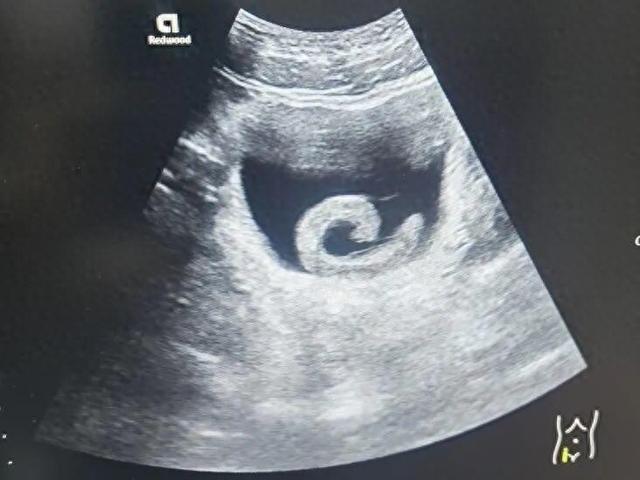

23岁男子信偏方把5cm水蛭塞进尿道!近日,河南郑州一名23岁的年轻人小郑在网上看到一些所谓的“偏方”后,出于好奇和猎奇心理,竟然网购了一条活体水蛭并将其塞入了自己的尿道。起初,他期待某种“奇特”的效果,但很快剧烈的疼痛和排尿困难让他意识到问题的严重性。水蛭顺着尿道爬到了膀胱,并开始吸血和释放抗凝血物质。小郑随即前往郑州市人民医院就诊。

泌尿外科副主任医师马曜辉为小郑进行了经尿道膀胱异物取出术,手术顺利,解除了尿道梗阻,小郑的疼痛也瞬间消失。事后,小郑对自己的行为感到后怕和悔恨。